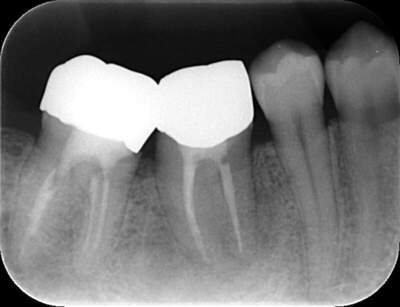

レントゲン写真

根管治療後3ヶ月です。根のまわりの骨がやや白くなってきているのがわかります。だんだん骨の添加がみられている証拠になります。

ここまで治癒していればかぶせ物をかぶせても問題ないと判断しました。

最後のレントゲンでは、骨がしっかり添加され、周囲組織となんら変色ない状態にまでなっていることがわかる。